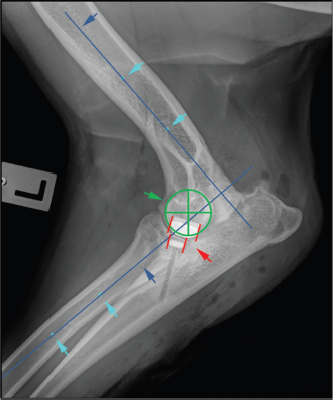

Parallelism of the implants contact surface in the coronal plane was measured on the CrCd view. First, a line parallel to the surface of the HImpl and a second line identical with the longitudinal axis of the elliptically projected metallic base of the UImpl were drawn. The angle between those two lines is reported as medial or lateral opening angle, depending on whether the angle was open towards the medial or lateral aspect of the joint (Fig. 2).

Fig. 2. Determination of implant parallelism showing a medial opening angle α=7°. First-line lies parallel to the surface of the HImpl and a second line is identical with the longitudinal axis of the elliptically projected metallic base of the UImpl.

Cranio-caudal overlap of both implants was measured on ML views (Figs. 3 and 4).

First, the humeral longitudinal axis was drawn, as a line connecting the midpoints between both humeral cortices at 50% and distal 30% of its length. The radial longitudinal axis was determined by applying the same principle. A goniometer template was then positioned with each arm parallel to the respective longitudinal axis with the center of rotation at the center of the humeral condyle. Cranial and caudal edges of the implants were then marked on the template (Fig. 3). While the humeral arm of the template remained fixed, the radial arm with marked UImpl edges was first brought into full extension, positioning the ulnar implant caudal to the humeral one and then gradually flexed back to full flexion in order to mimic the full range of elbow motion. Extension angles for six elbow positions were recorded (Fig. 4):

1. Extension angle with no overlap between UImpl and HImpl, with the HImpl just cranial to the ulnar implant (Fig. 4A).

2. Extension angle with 50% UImpl overlap (Fig. 4B).

3. Extension angle with the caudal part of the HImpl overlapping 100% of the UImpl (Fig. 4C).

4. Extension angle with the cranial part of the HImpl overlapping the whole UImpl (Fig. 4D).

5. Extension angle with 50% UImpl coverage (Fig. 4E)

6. Extension angle with no overlap between UImpl and HImpl, with the HImpl just caudal to the ulnar implant (Fig. 4F).

The difference between the largest and the smallest extension angle measured represents the range of elbow motion with implant overlap and is termed the implant contact phase span (ICPS). In cases with multiple ulnar implants, these measurements were repeated, with the caudal border of the most caudal UImpl and the cranial border of the most cranial UImpl set as reference.

Fig. 3. Determination of long bone axis as well as joint rotation center for measurement of cranio-caudal humero-ulnar implant overlap turquoise arrows: midpoints between cortices at 50% and 30% of the humeral and radial bone length; blue arrows: longitudinal bone axis of humerus and radius; green cross: center of elbow joint rotation, identical with center of humeral condyle; red lines: cranial and caudal edge of the humeral and ulnar implants.

Fig. 4. Measurement of simulated elbow joint extension angle for six states of cranio-caudal humero-ulnar implant overlap, starting with full extension. (A) No overlap between ulnar and humeral implant, with the ulnar implant just caudal to the humeral one; (B) coverage of the cranial half of the ulnar implant (50%); (C) largest extension angle with 100% ulnar coverage; (D) smallest extension angle with 100% ulnar coverage; (E) coverage of the caudal half of ulnar implant (50%); and (F) no overlap between ulnar and humeral implant, with the ulnar implant just cranial to the humeral one. α: measured extension angle.